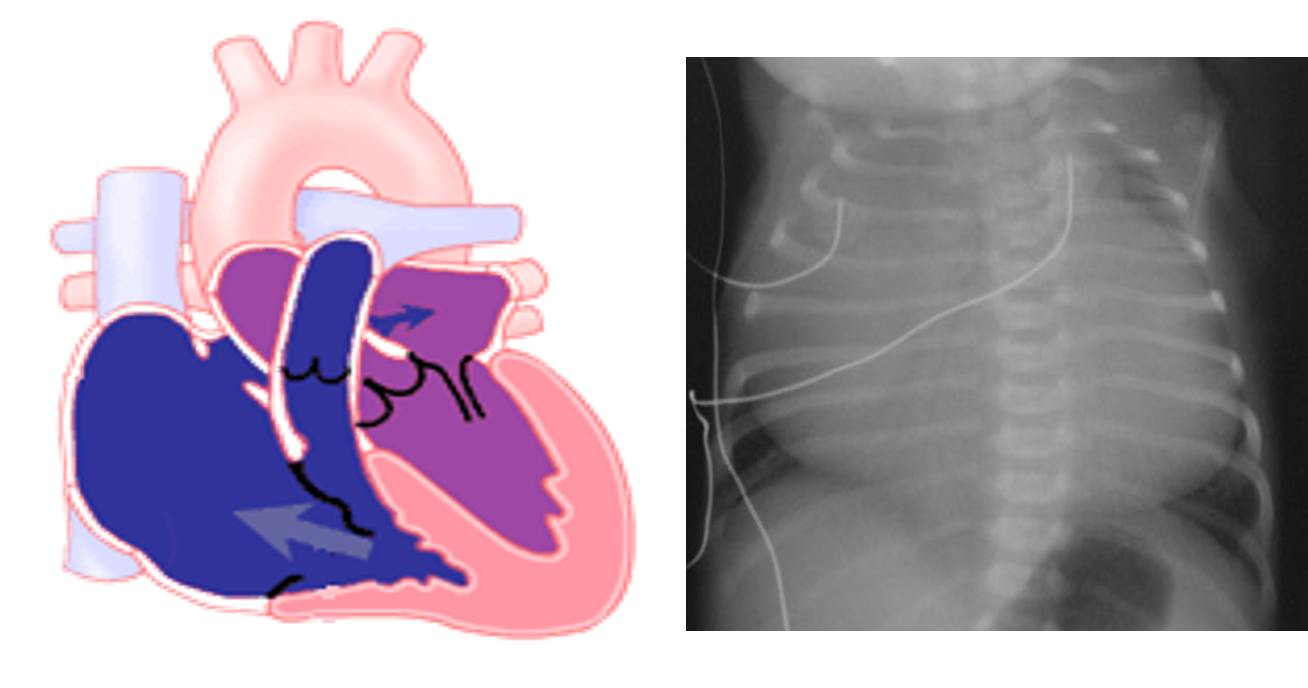

Ebstein’s Anomaly